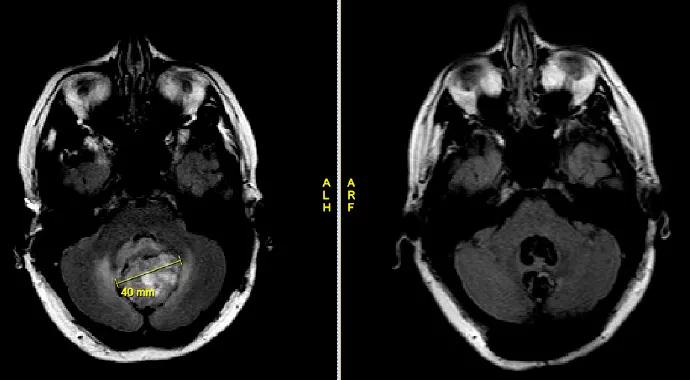

An MRI revealed a large cerebellar hemorrhagic mass with resultant obstructive hydrocephalus. She was then transferred to Cleveland Clinic’s Rose Ella Burkhardt Brain Tumor and Neuro-Oncology Center for further care.

Based on the size of tumor and the presentation with increased intracranial pressure, the neurosurgery team determined it was not safe to wait to perform surgery until after term delivery. Thus, we decided to proceed with surgery to remove the tumor two days after the patient was admitted and after pre-operative optimization was performed.

A postoperative MRI showed complete resection of the tumor. Pathology revealed the tumor was benign, and no postoperative radiation or chemotherapy would be required. The patient went home after a few days and delivered a baby girl two months after surgery, in her 36th week of pregnancy, after premature rupture of membrane. Both the patient and the baby are doing well.